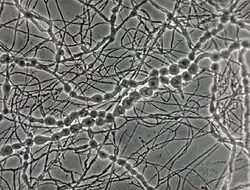

The growth of M. mycetomatis is very slow and can be broken down into three stages. Initially the colony is dome shaped white-yellow or olivaceous brown in color.[9] The mycelium is covered in grey down, giving it a woolly texture. Following the initial stage, brownish aerial mycelia (1 to 5 μm) form and the colony starts producing a diffusible pigment called pyomelanin, and becomes smooth in texture.[3] Older colonies form masses of hyphae called sclerotia or grains. In nutritionally deficient or potato-carrot media, black grains (0.75 to 1 mm in diameter) with undifferentiated polygonal cells can be observed.[8][9]

Grains of M. mycetomatis are hard and brittle, ranging between 0.5 and 1 mm (maximum being 2 mm), with masses from 2 to 4 mm. The grains are oval and often multi-lobed. They are reddish brown to black in color and texturally smooth or ridged.[9][11] The grains are made up of an internal mass of hyphae, 2 to 5 μm in diameter, with terminal cells swelling from 12 – 15 μm (maximum being 30 μm) in diameter.[8] Overall two main types of grains are observed. The most common type is compact or filamentous, where a dark brown cement like amorphous, electron rich substance fills the voids surrounding the hyphal network.[9] The hyphal network differs in growth between the cortical and medullar region, with radial versus multidirectional growth respectively. When stained with hematoxylin and eosin it appears rust-brown in color. In contrast, the second type, vesicular, has a light colored medulla and a brown cortical region filled with hyphae and vesicles 6 to 14 μm in diameter.[12] Often it is difficult to determine the transition point from cortex to medulla. Lesions can have both the filamentous and vesicular type grains at the same time.[3][8]

Although conidiation (conidium), a form of asexual reproduction, in M. mycetomatis is rare, two main types can be described in-vitro. In the first type oval to pyriform conidia, 3 to 5 μm can be observed. The conidia have truncated bases and are on the tips of simple or branched conidiophores. In-vitro, this type of conidiation can be observed in 50% of cultures on soil extract, hay infusion or water agar.[9] When grown on potato carrot agar or cornmeal agar the second type of conidiation is observed. This type is characterized by small spherical conidia (3 μm in diameter) on tapered tips of flask shaped phialides and collarettes.[8][13] On SDA media M. mycetomatis is sterile.[3][9] No sexual stage has been identified for M. mycetomatis.[6]